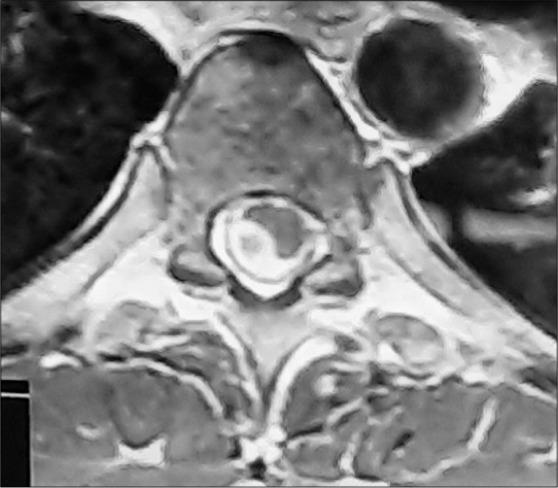

A 25-year-old male with human immunodeficiency virus, hepatitis C virus, and disseminated TB on antitubercular therapy for the past 8 months, presented with paraplegia of 2 months duration. When the MRI spine revealed multiple peripheral rim enhancing intradural extramedullary lesions from T6 to T8 and dorsally from T10 to T11, the patient was diagnosed with IETSC. At surgery, we countered cystic lesions adherent to the dura and the spinal cord, containing a whitish material. Postoperatively, the patient showed clinical improvement in motor power and sensation.

一名25岁男性,感染人类免疫缺陷病毒、丙型肝炎病毒,过去8个月一直在接受抗结核治疗,患有播散性结核病,出现了持续2个月的截瘫症状。当脊柱MRI显示从T6至T8以及从T10至T11背侧有多个周边环形强化的硬膜内髓外病变时,该患者被诊断为IETSC。手术中,我们遇到了与硬脑膜和脊髓粘连的囊性病变,其中含有白色物质。术后,患者的运动能力和感觉在临床上有所改善。